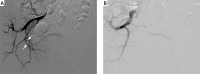

Figures